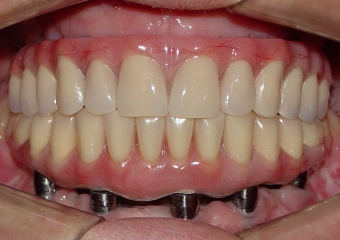

Próteses fixas superior e inferior, sobre implantesdo caso finalizado em janeiro de 2011

Sorriso final